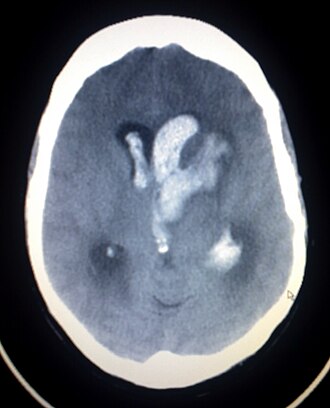

| BT ile çekilmiş bir spontan intrakranial kanama | |